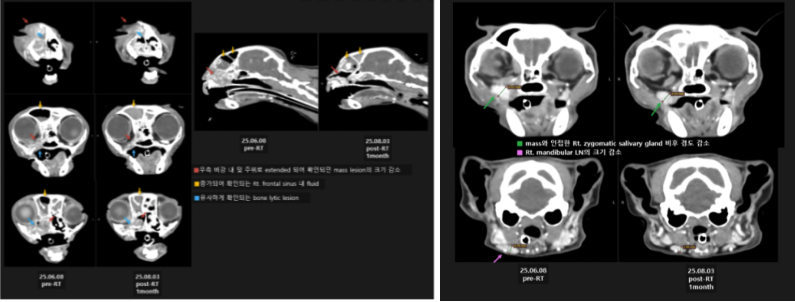

01 고양이 구강 편평세포암종 진단

정확한 환자 상태 평가 및 확정진단을 위하여 전신 CT 촬영 및 조직 검사를 계획하였습니다.

📌CT 검사 결과

이번 영상 검사에서 확인된 병변은 위턱뼈(상악)에서 시작된 병변일 가능성이 가장 높습니다. 뼈가 녹아내리는 모습(bone lysis)과 뼈 표면이 반응하는 소견(periosteal reaction)이 보여, 악성 종양일 가능성을 우선적으로 고려해야 합니다.

다만, 코(비강)에서 시작된 병변이 위턱뼈로 퍼진 것일 가능성도 완전히 배제할 수는 없습니다. 따라서 정확한 원인을 알기 위해서는 조직 검사가 필요합니다.

02 조직 검사 결과

환자는 비강 유래 종양보다는 구강 상악 유래 종양의 비강 및 안와 침범이 의심되었으며, 유의적인 전이 소견이 뚜렷하게 확인되지 않았습니다.

이어 진행한 조직 검사 결과에서 편평세포암종(SCC) 확정 진단되었습니다.

이미 종양이 주변 조직을 심하게 침습해 근치적 수술은 불가능했습니다. 하지만 종양 위치가 비교적 rostal(앞쪽) 부위인 점과 진단 당시 환자의 통증이 매우 심한 상태였기 때문에 보호자와 상담 끝에 방사선치료를 시도하기로 결정했습니다.